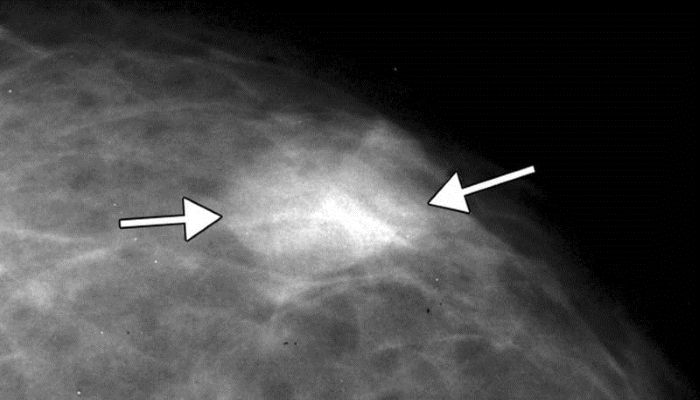

- Маммография.

На маммограмме четко видны увеличенные опухоли, так как со временем новообразование накапливает кальциевые соли. Это позволяет не только оценить размеры и контуры опухоли, но и определить сроки ее роста.